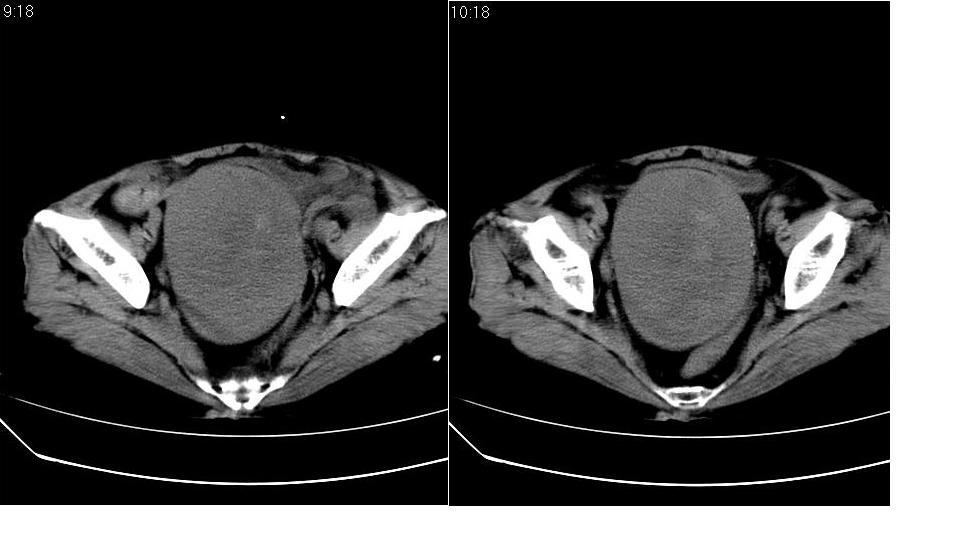

女,70岁,十天前在上级医院确诊宫颈癌,具体病史不详。

子宫形态增大,其内密度不均匀,宫颈部未见异常

子宫体积增大,其内密度不均,考虑子宫内膜癌侵犯宫颈

宫颈癌阻塞性宫腔积液?累及宫腔?

子宫增大可以是肌瘤的改变,宫颈癌多为鳞癌,子宫内膜癌多为腺癌。